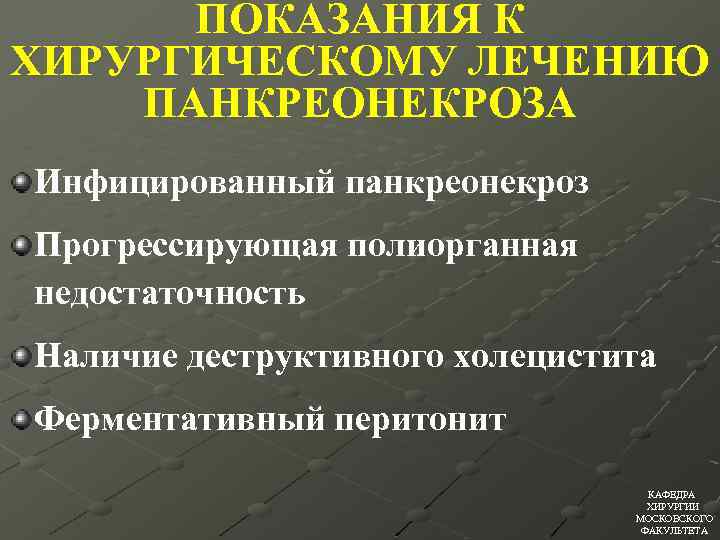

ПОКАЗАНИЯ К ХИРУРГИЧЕСКОМУ ЛЕЧЕНИЮ ПАНКРЕОНЕКРОЗА Инфицированный панкреонекроз Прогрессирующая полиорганная недостаточность Наличие деструктивного холецистита Ферментативный перитонит КАФЕДРА ХИРУРГИИ МОСКОВСКОГО ФАКУЛЬТЕТА

ПОКАЗАНИЯ К ХИРУРГИЧЕСКОМУ ЛЕЧЕНИЮ ПАНКРЕОНЕКРОЗА Инфицированный панкреонекроз Прогрессирующая полиорганная недостаточность Наличие деструктивного холецистита Ферментативный перитонит КАФЕДРА ХИРУРГИИ МОСКОВСКОГО ФАКУЛЬТЕТА